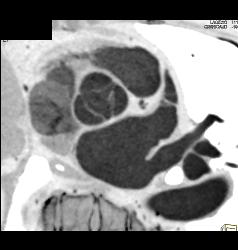

SVC Occlusion With Collaterals. SVC Occlusion Was Due to Tumor